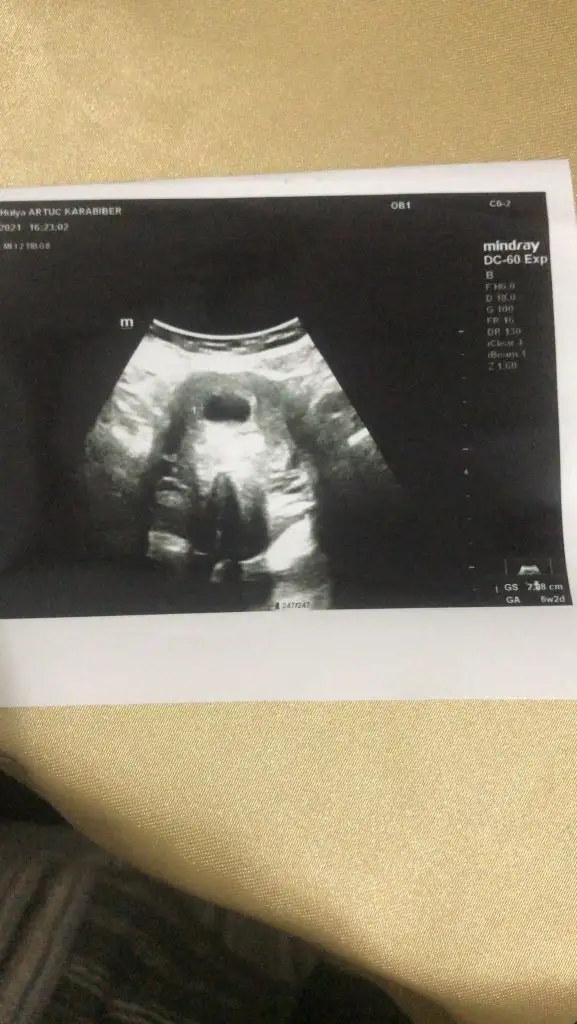

Ikra meyra Ikra meyra canim buda bi arkadasimin onunki ne de tahminde bulunur musn?

• 16234053727003850929089284363744.webp

16234053727003850929089284363744.webp

18,4 KB · Görüntüleme: 57